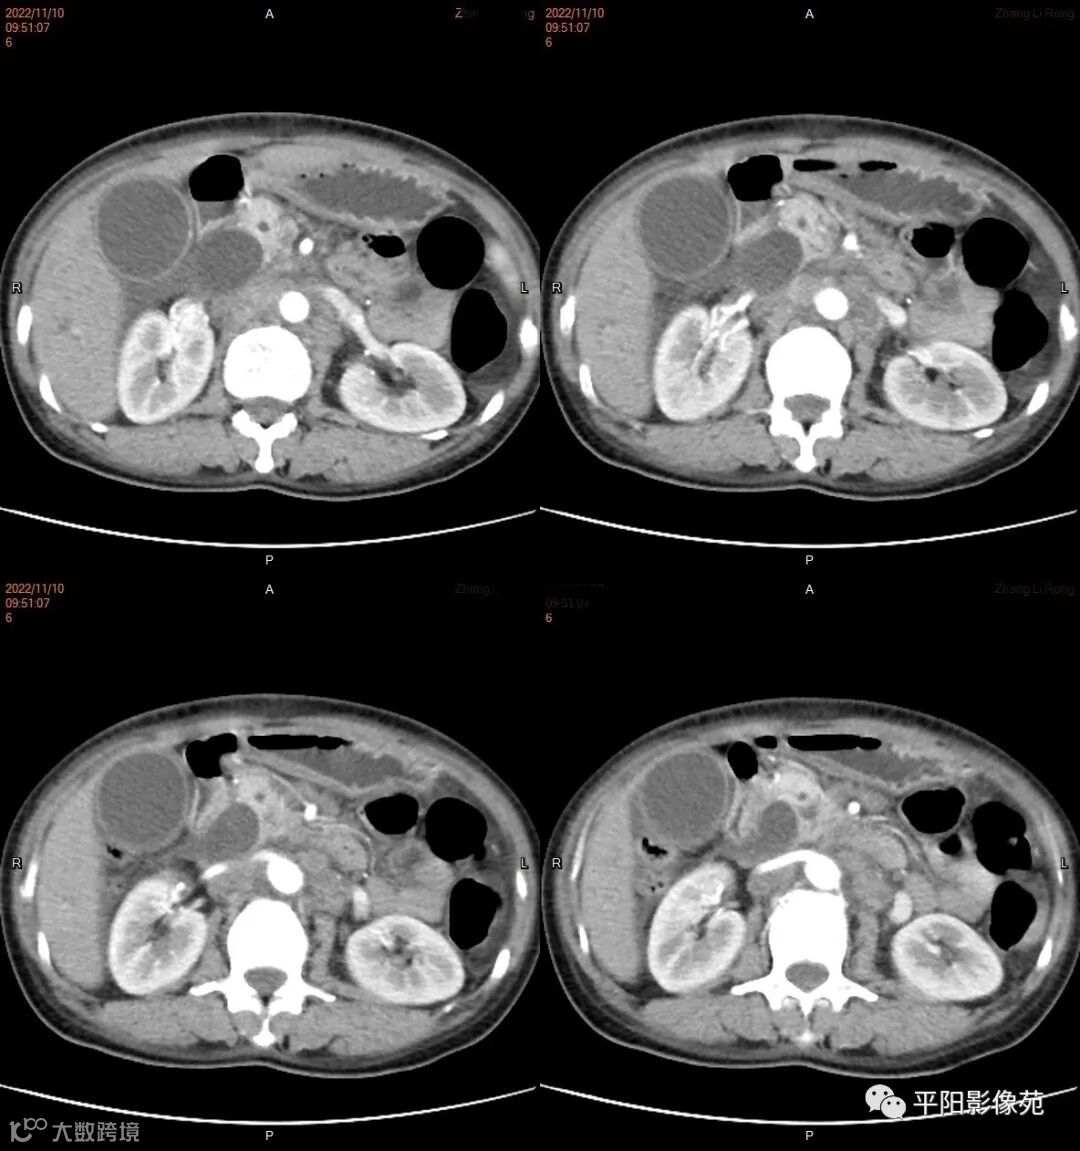

影像学检查

CT

影像表现: